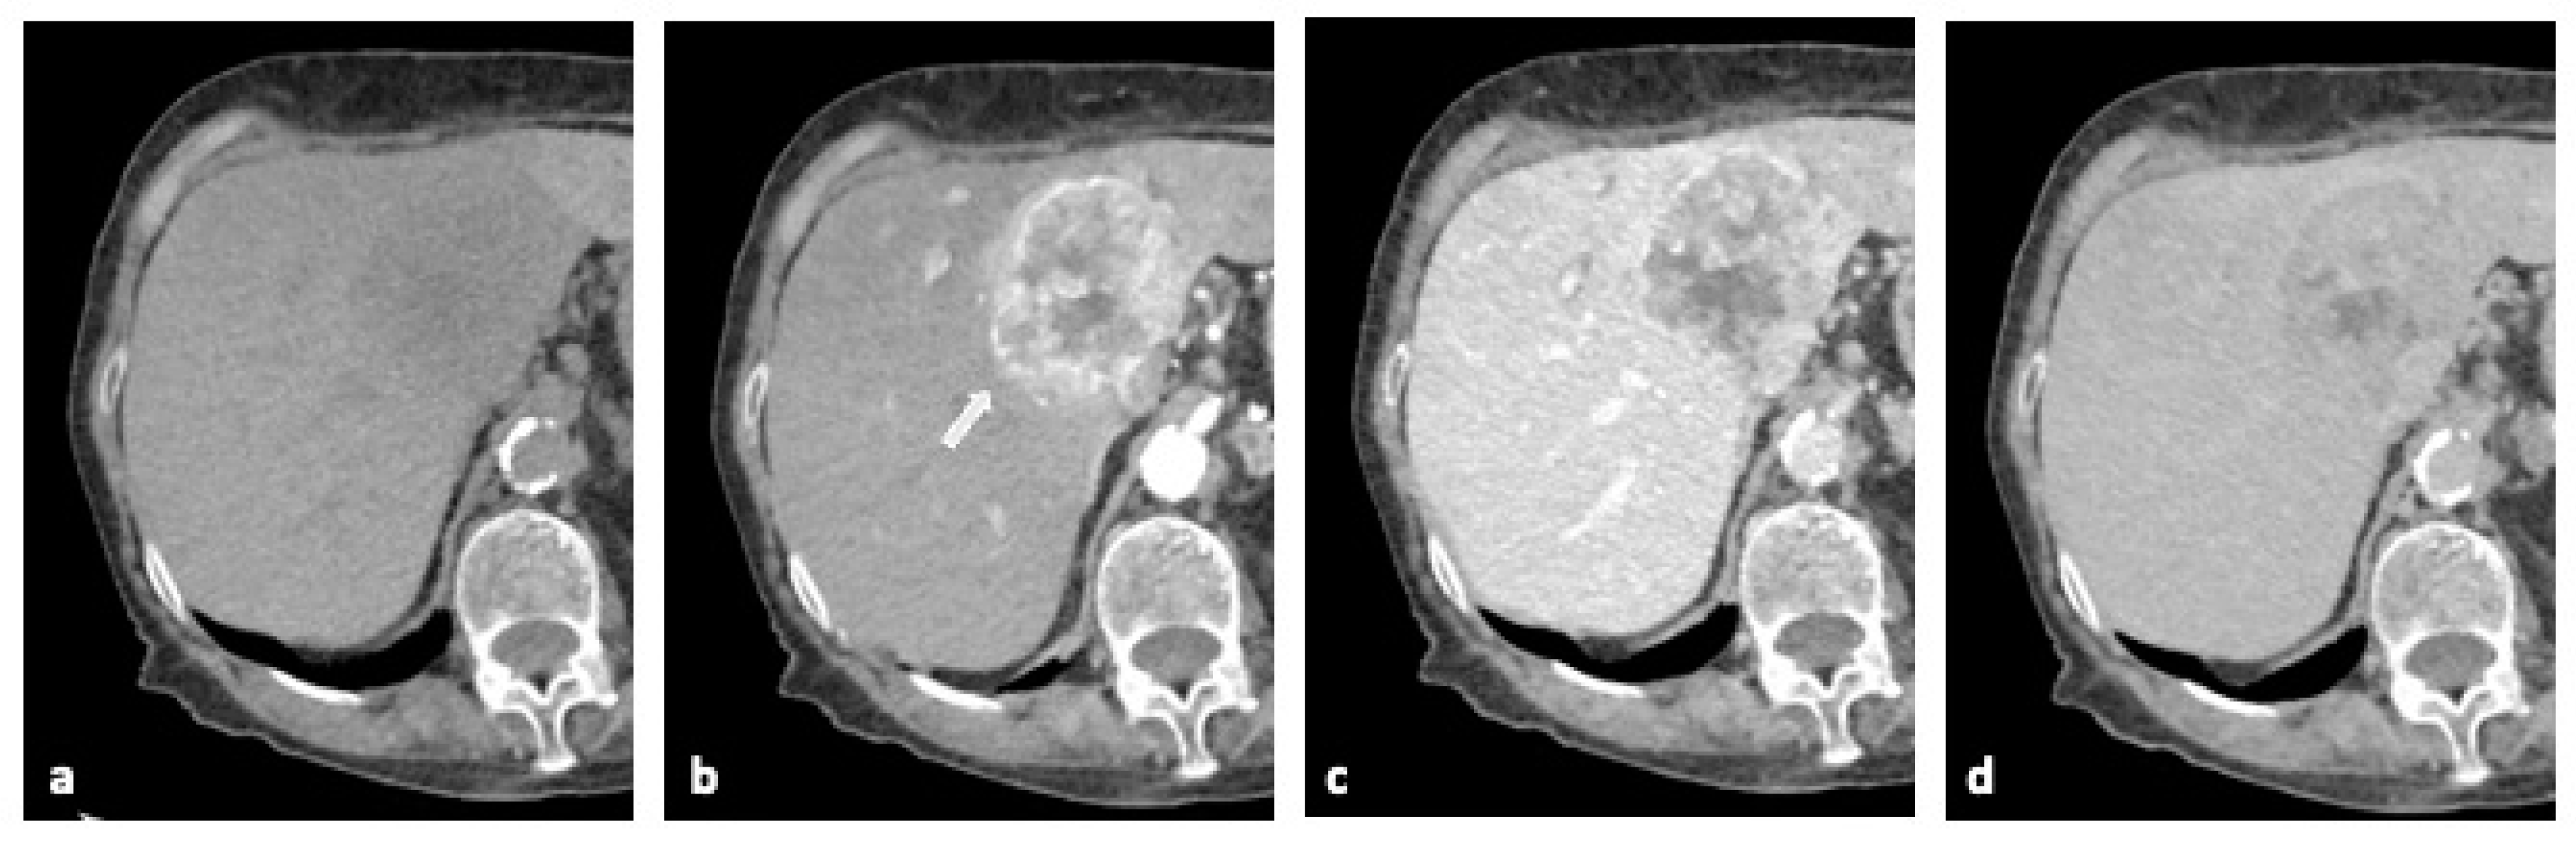

2.2. Computed Tomography (CT)

- Olthof, S.C.; Othman, A.; Clasen, S.; Schraml, C.; Nikolaou, K.; Bongers, M. Imaging of Cholangiocarcinoma. Visc. Med. 2016, 32, 402–410. [Google Scholar] [CrossRef]

- Chung, Y.E.; Kim, M.J.; Park, Y.N.; Choi, J.Y.; Pyo, J.Y.; Kim, Y.C.; Cho, H.J.; Kim, K.A.; Choi, S.Y. Varying appearances of cholangiocarcinoma: Radiologic-pathologic correlation. Radiographics 2009, 29, 683–700. [Google Scholar] [CrossRef] [PubMed]

- Saleh, M.; Virarkar, M.; Bura, V.; Valenzuela, R.; Javadi, S.; Szklaruk, J.; Bhosale, P. Intrahepatic cholangiocarcinoma: Pathogenesis, current staging, and radiological findings. Abdom. Radiol. 2020, 45, 3662–3680. [Google Scholar] [CrossRef]